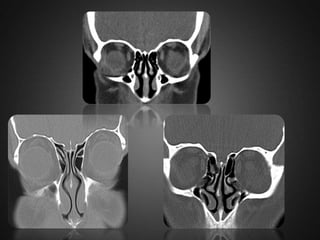

Uncinate process  Theuncinate process is a superior extension of the lateral nasal wall that is anatomically relevant for draining the frontal recess.  Variations such as hypertrophy, deviation and pneumatization may affect the drainage, generating abnormalities in the osteomeatal complex.

 A)horizontal uncinate b)hypertrophy of lt uncinate.  C)pneumatisation of lt uncinate.  D)vertical lt uncinate.